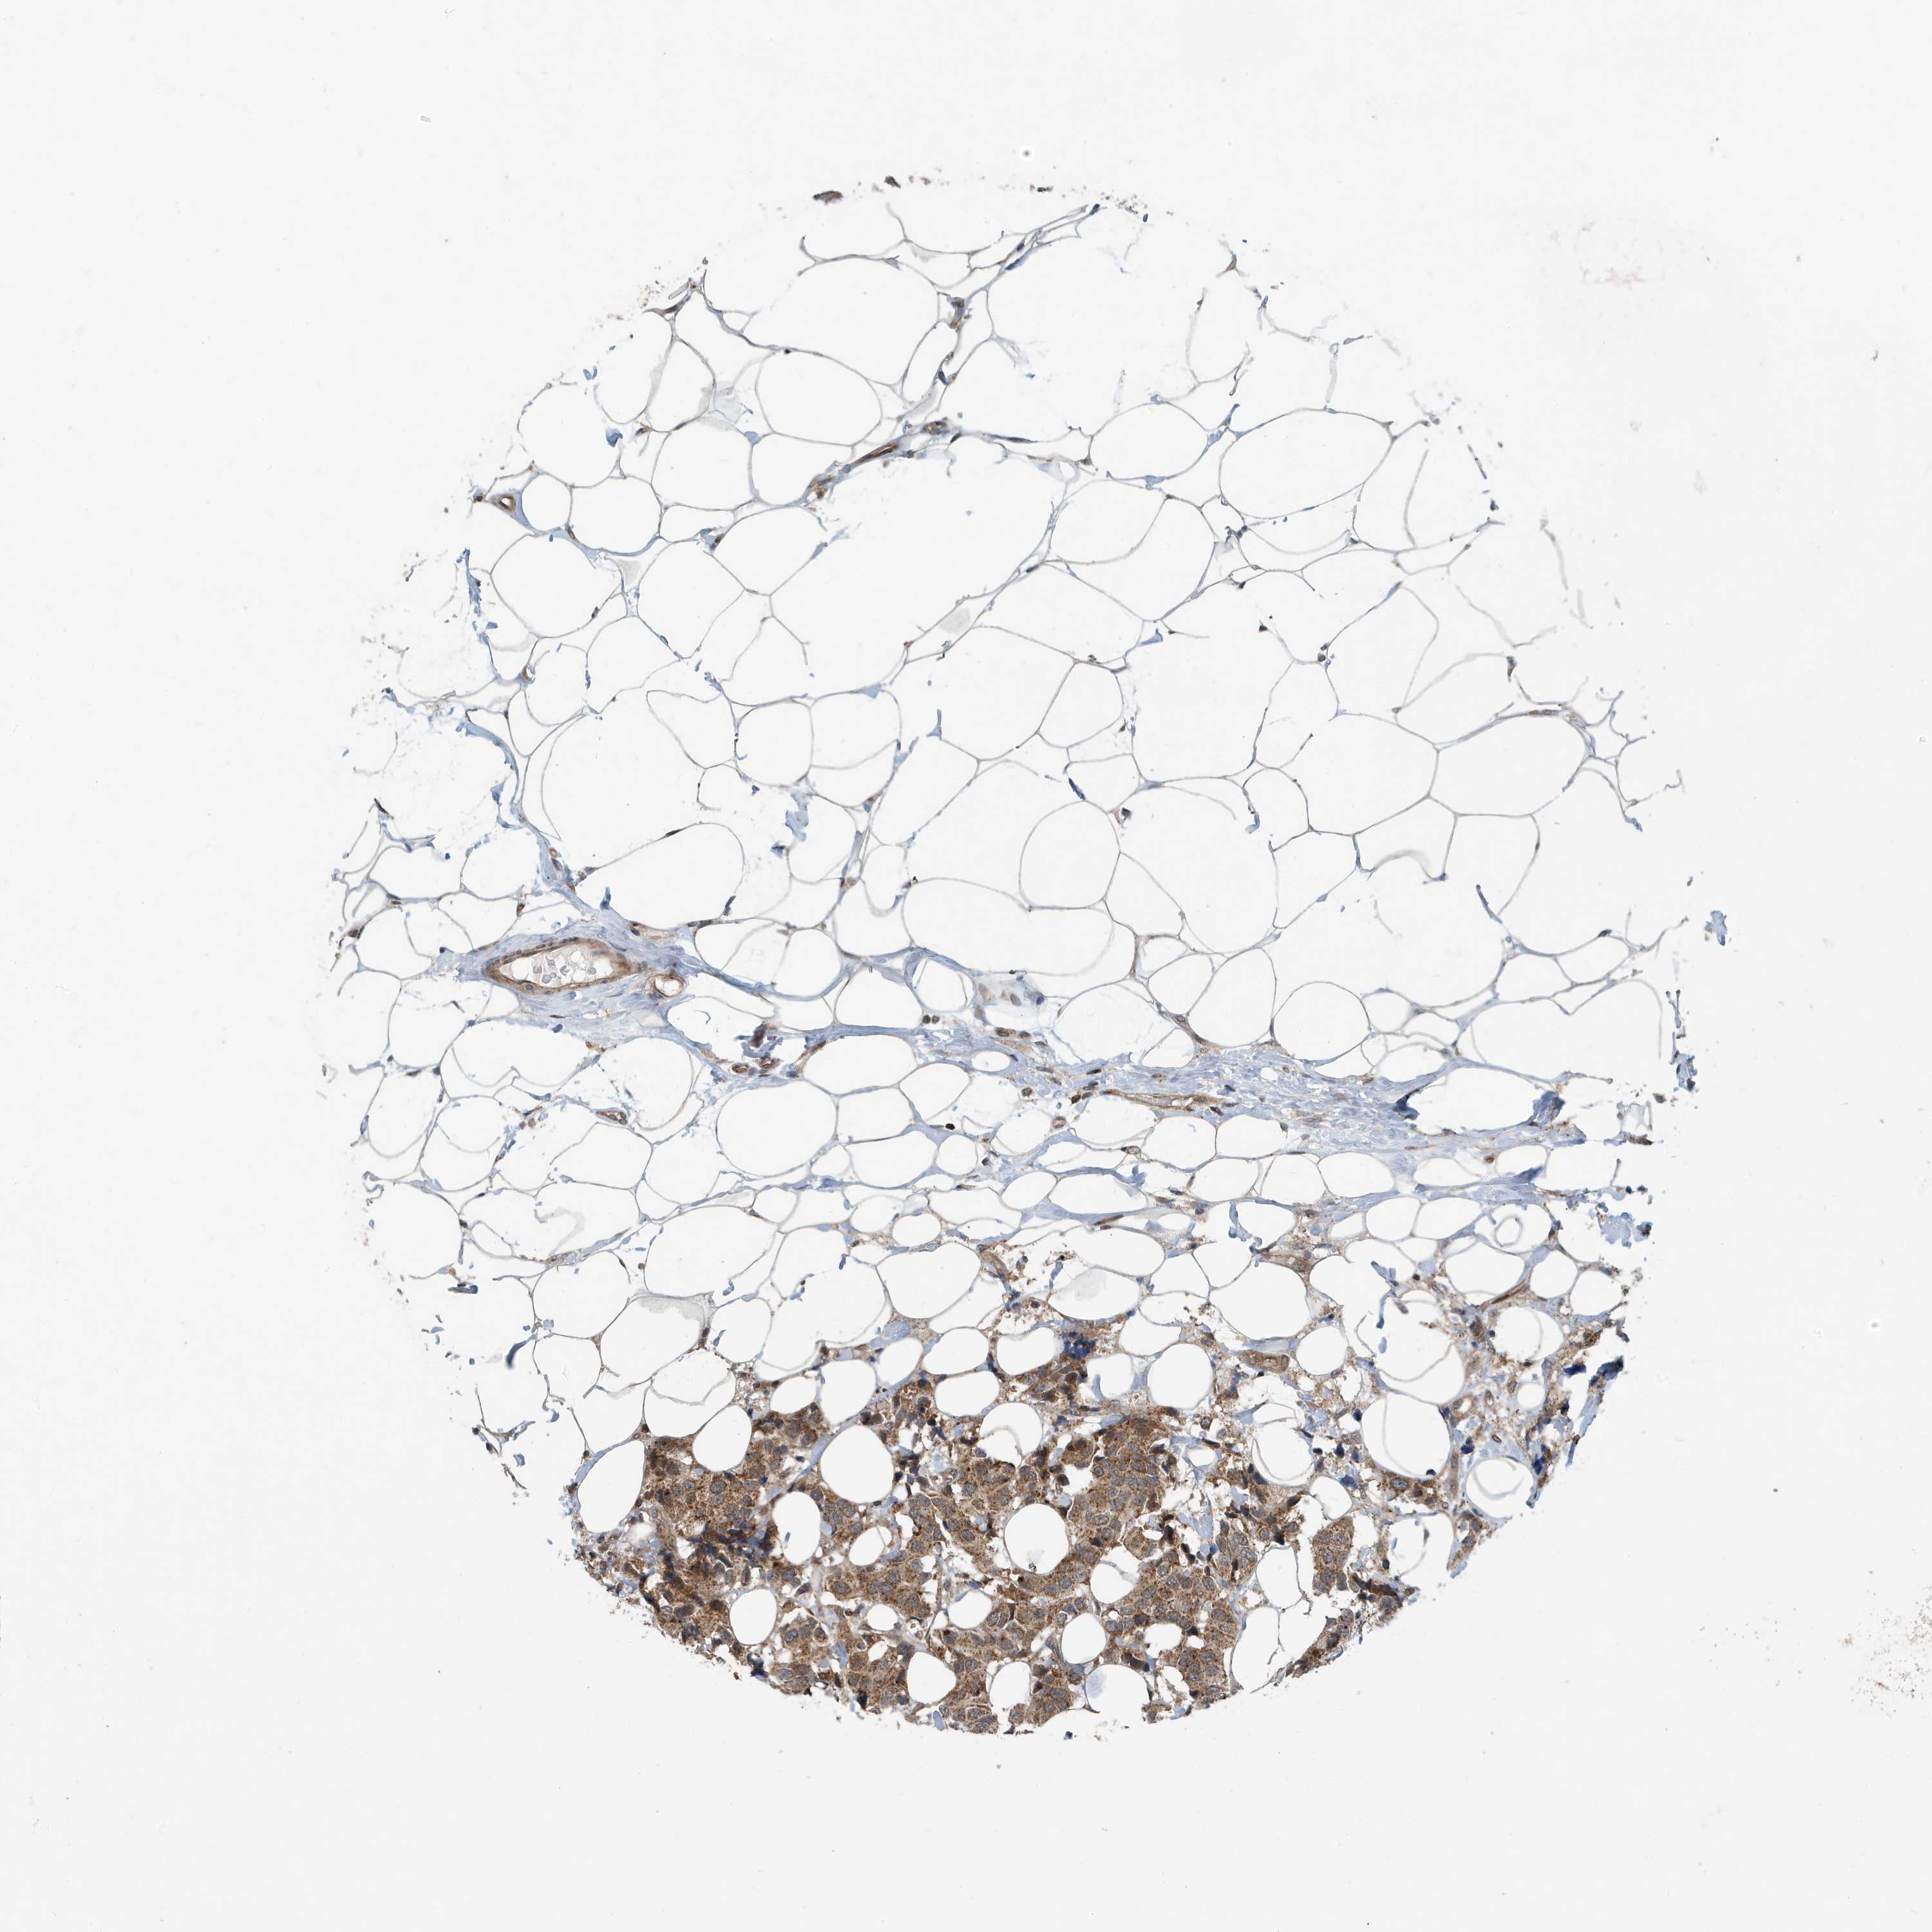

BRCA TCGA BRCA VALIDATION PROTEIN EXPRESSION